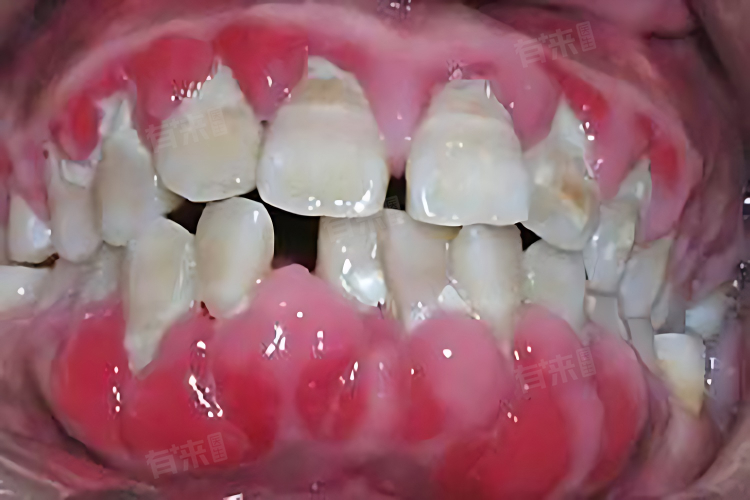

牙周袋是指牙齿根部附近的牙龈组织发生炎症,导致牙龈与牙齿之间的间隙扩大,扩大的间隙容易积聚细菌和食物残渣,进一步加重病情。